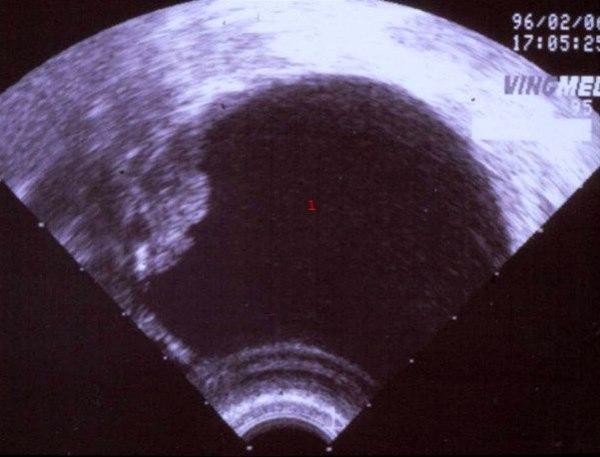

Cystadenofibrom

1. Cyste, væskefullt hulrom